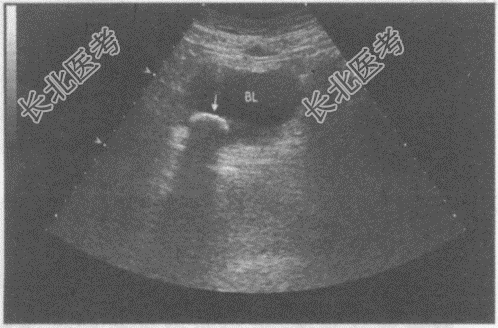

- 单项选择题临床资料:男, 65岁,自述排尿不尽, 尿流中断3月余,尿频, 尿痛伴血尿2天。既往有慢性前列腺增生病史。

超声综合描述:膀胱充盈好, 腔内可见2.1cm弧形强回声光带,后伴声影, 可随体位变化而移动(箭头所示)。

超声提示: A、膀胱内血块

B、膀胱结石

C、膀胱癌

D、右输尿管结石

E、膀胱囊肿